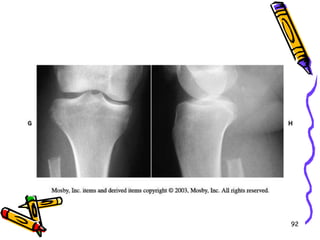

51 year old lady  c/o knee pain88

T1 weighted MRI revealed lesion within fibula and no breaching of cortex89

Primary resection was done without biopsy 90

This treatment strategy allowed for wide marginal excision without contamination of common peroneal nerve Lesion proved to be low grade  chondro sarcoma 91

92